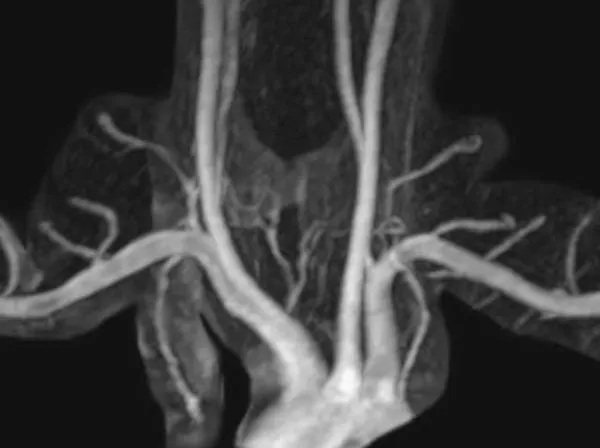

MR angiography is performed by injecting contrast into a peripheral vein, without an arterial catheter. MRA shows excellent arterial detail while eliminating most other structures, including bones. It requires no radiation. If used in conjunction with MRI, superb soft tissue detail is available. Excellent depiction of fibrous bands, muscle anomalies, bones, and the brachial plexus is possible with MRI.

This interactive media demonstrates magnetic resonance angiography (MRA) images in two different patients. One patient has a normal MRA. The other patient has compression of each subclavian artery. Note that the structures that cause this compression are not visible on MRA alone.